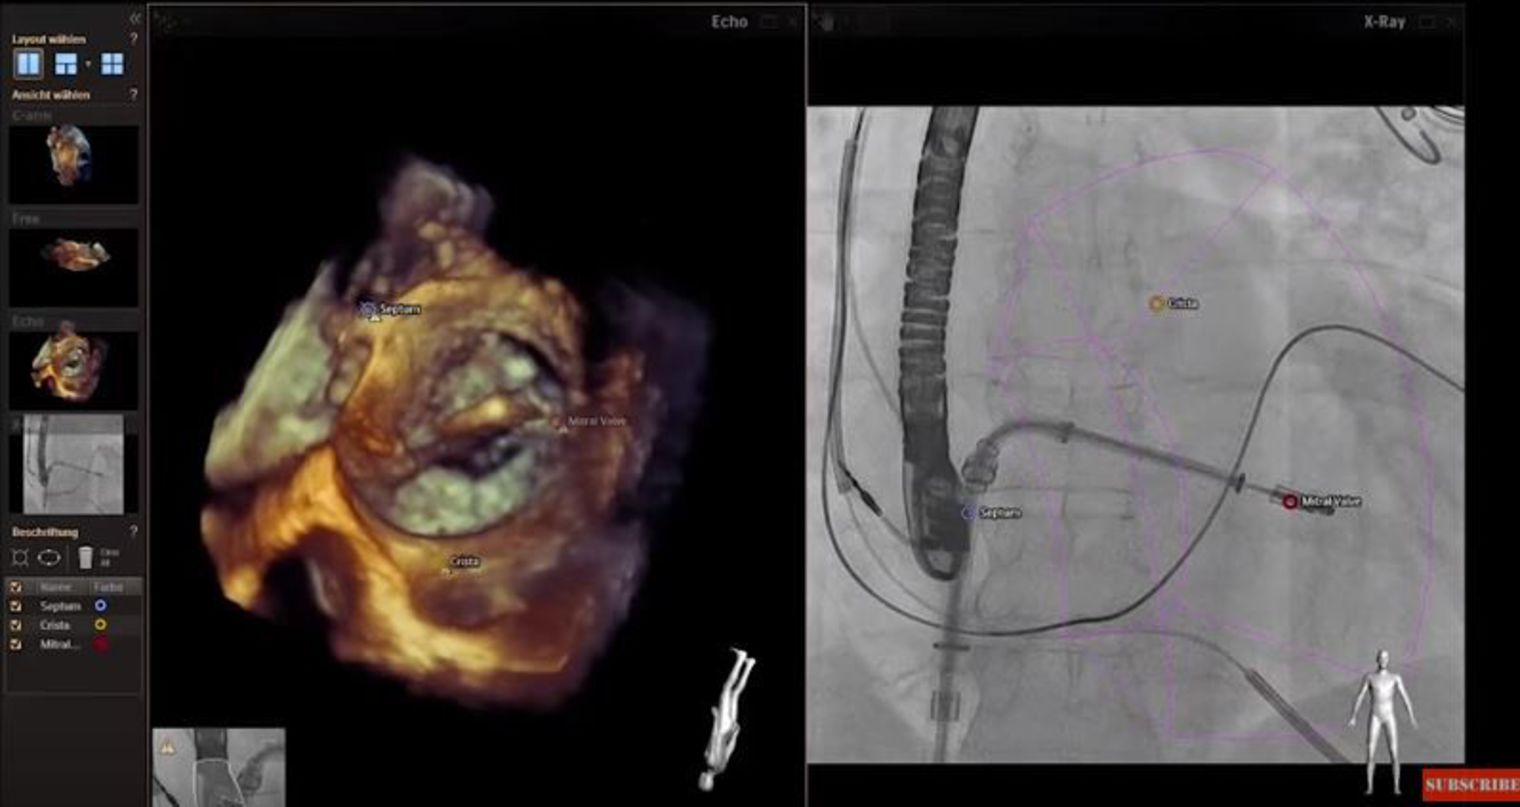

Tehnologia, dezvoltata de Philips, si care se integreaza intr-un proiect European, permite afișarea pe același ecran și în 3D a ecografiei inimii copilului și a razelor X în momentul în care medicii introduc sonda pe care o folosesc pentru repararea malformațiilor cardiace, a explicat profesorul Acar, care conduce proiectul de cercetare clinică.